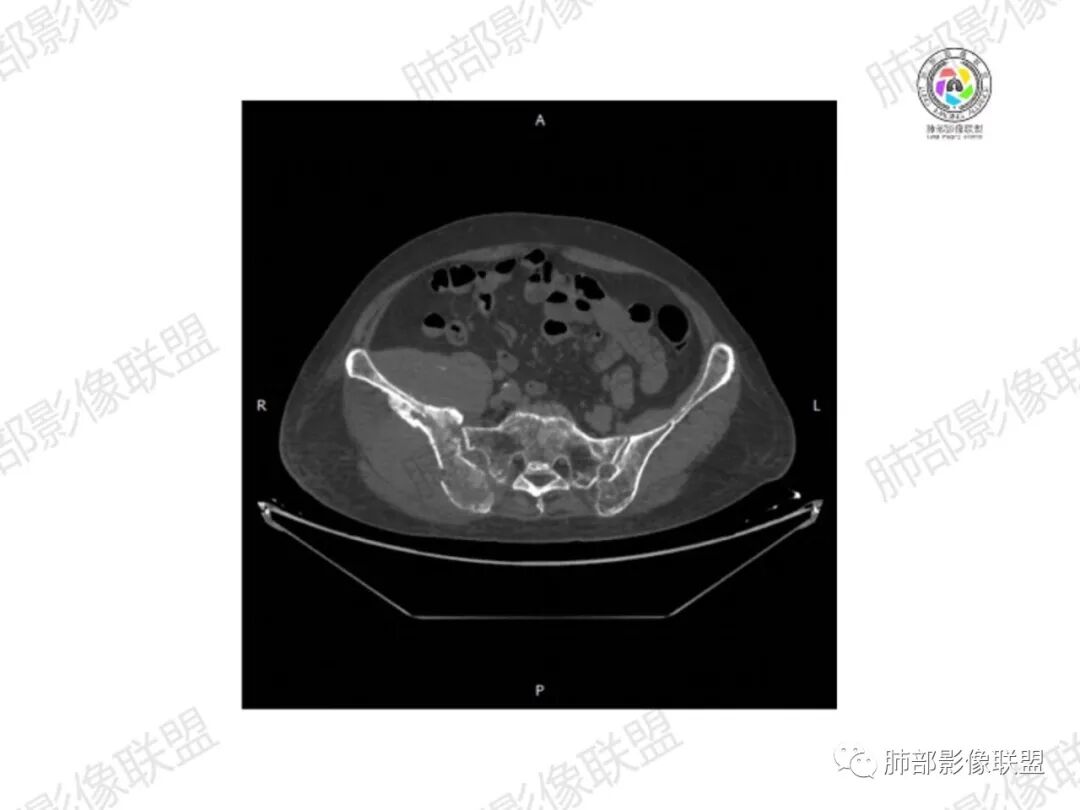

1.老年女性,直肠癌术后放疗后5年,右臀部疼痛4个月,加重半月

2.右髂骨轻度变形伴广泛骨质吸收破坏,边界不清且突破骨皮质。近中线区以溶骨性破坏为主,髂骨翼一侧则成骨性改变明显,骨表面见垂直骨针或花边样高密度瘤骨。

3.患骨多处皮质断裂,符合病理性骨折。注意折端可能会形成骨痂,但本例无论是形态还是部位都不符合骨痂。

4.患骨两旁(即盆骨内外)见边界不清的较大范围软组织快影,其间偶见骨化影。

1.边界不清的骨质吸收破坏,溶骨明显,骨皮质突破,软组织肿块,种种迹象表明其恶性无疑!

2.但注意这是有“成骨”的恶性骨肿瘤!我们知道老年患者的骨原发性恶性肿瘤“成骨”非常少见。少数转移瘤可为成骨型或混合型,女性患者如乳腺癌骨转移等。在男性,最典型的成骨转移是前列腺癌。

本例右侧髂骨具有较为典型的“骨肉瘤”影像学特征,有边界不清的吸收破坏、有新生骨、形成软组织肿块等等。

4.“成骨肉瘤”绝大多数发生于青少年,发生于老年患者则往往见于其他因素,如诱发于畸形性骨炎(Paget病,本例影像不支持),骨照射、骨坏死等。其他如骨旁骨肉瘤等,发病年龄可以偏大。